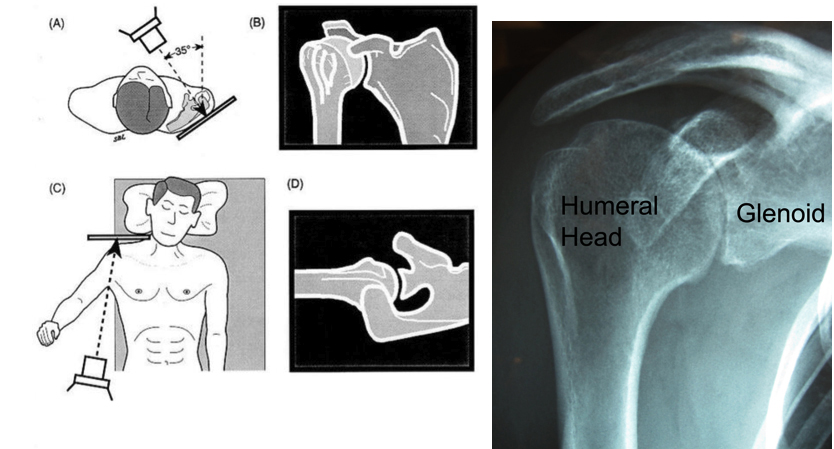

Summary The ream and run procedure can restore comfort and function to the arthritic shoulder. In this procedure the arthritic ball is replaced by a smooth metal ball fixed to the arm bone (humerus) by a stem that fits within it. The bone of the arthritic socket is reamed to the desired shape and allowed to heal with a biological surface during the period of recovery after surgery. This proce- dure avoids the possible risks and limitations associated with a plastic socket replacement and with the cement used to fix it in position. Success requires technical excellence of the surgery and a steadfast commitment to the exercise program until the desired range of motion can be achieved comfortably. What Are The Key Parts Of The Normal Shoulder Joint? The ball (humeral head) fits in the socket (glenoid) and is held there by the rotator cuff. What Is Shoulder Arthritis? Shoulder arthritis is a condition in which degeneration injury inflammation or previous surgery destroys the normally smooth cartilage on the ball (humeral head) and socket (glenoid). How Is Shoulder Arthritis Diagnosed? Carefully standardized X-rays reveal the loss of the space between the humeral head and glenoid that is normally occupied by cartilage leaving bone on bone contact. What Is A Total Shoulder? In a total shoulder the arthritic surface of the ball is replaced with a metal ball with a stem that fits down the inside of the arm bone (humerus) and the socket is resurfaced with a high density polyethylene component. While this is a standard treatment for arthritis of the shoulder it does carry the possible risk that the plastic glenoid component will wear loosen or break over time especially with heavy use. What Is A "Ream And Run" Surgery For Shoulder Arthritis? In a ream and run the bone of the socket is shaped with a reamer so that a smooth concavity results. The arthritic surface of the ball is replaced with a metal ball with a stem that is press fit down the inside of the arm bone (humerus) so that only the smooth surface extends from the bone. After a general or regional anesthetic this procedure is performed through an incision between the deltoid and the pectoralis major muscles on the front of the shoulder. It includes release of adhesions and contractures and removal of bone spurs that may block range of motion. Our team of surgeons anesthesiologists and surgical assistants usually perform this procedure in less than two hours. Our shoulder therapists begin teaching the rehabilitation program the day of surgery. How Is The Humeral Component Fixed In The Humerus? While some surgeons cement the humeral component and others use implants that foster bone ingrowth we find that these approaches stiffen the bone making it more likely to fracture in a fall on one hand and greatly complicating any revision surgery that may become necessary in the future on the other. We prefer to fix the component by impaction grafting the inside of the humerus (using bone harvested from the humeral head that has been removed) until a tight press fit of the implant is achieved. What Happens To The Raw Bone Surface Left After The Reaming Of The Glenoid? Laboratory studies at the University of Washington have shown that the reamed glenoid can heal over with a smooth fibrocartilagenous surface. Evidence that similar regeneration occurs in patients comes from the space shown on x-rays between the metal ball and the bony socket. In order for proper healing to occur the patient must maintain the range of motion achieved at surgery with simple frequent stretching exercises. Rehabilitative exercises are started immediately after surgery using continuous passive motion and stretching by the patient. Attaining and maintaining at least 150 degrees of forward elevation is critical to the success of this procedure. The forward lean and the supine stretch can be helpful in getting there and maintaining this range of motion. Who Should Consider A Ream And Run? Surgery for shoulder arthritis should only be considered when the arthritis is limiting the quality of the patient's life and after a trial of physical therapy and mild analgesics to determine if non-operative management is helpful. Severe arthritis is usually best managed by either a partial or a complete joint replacement. The ream and run procedure may be considered by patients who are willing to put in substantial extra time and effort in the rehabilitation process to assure that proper healing occurs and who recognize that the pain relief and range of motion achieved with this procedure may not match that of a conventional total shoulder replacement. The ideal patient is healthy active motivated and committed to work diligently to achieve a shoulder reconstruction that does not require plastic and bone cement. Who Should Probably Not Consider A Ream And Run? This procedure is less likely to be successful in individuals with rheumatoid arthritis, depression, obesity, diabetes, Parkinson's disease, multiple previous shoulder surgeries, shoulder joint infections, rotator cuff deficiency and severely altered shoulder anatomy. Patients who use narcotic medication or who use tobacco are generally not candidates for this procedure. What Are The Keys To Success Of A Ream And Run? Success requires technical excellence of the surgery and a steadfast commitment by the patient to the exercise program until the desired range of motion can be achieved comfortably. How Does A Patient Prepare For The Ream And Run Procedure? As for all elective surgical procedures the patient should be in the best possible physical and mental health at the time of the procedure. Any heart lung kidney bladder tooth or gum problems should be managed before surgery. Any infection may be a reason to delay the operation. Any skin problem (acne scratches rashes blisters burns etc) on the shoulder or arm should be resolved before surgery. The shoulder surgeon needs to be aware of all health issues including allergies as well as the non-prescription and prescription medications being taken. For instance aspirin and anti-inflammatory medication may affect the way the blood clots. Some of these may need to be modified or stopped before the time of surgery. What Happens After Surgery? The ream and run is a major surgical procedure that involves cutting of skin tendons and bone. The pain from this surgery is managed by the anesthetic and by pain medications. Immediately after surgery strong medications (such as morphine or Demerol) are often given by injection. Within a day or so oral pain medications (such as hydrocodone or Tylenol with codeine) are usually sufficient. The shoulder rehabilitation program is started on the day of surgery. The patient is encouraged to be up and out of bed soon after surgery and to progressively reduce their use of pain medications. Hospital discharge usually takes place on the second or third day after surgery. Patients are to avoid lifting more than one pound pushing and pulling for six weeks after surgery. Driving is recommended only after the shoulder has regained comfort and the necessary motion and strength. This may take several weeks after surgery. Thus the patient needs to be prepared to have less arm function for the first month or so after surgery than immediately before surgery. For this reason patients usually require some assistance with self-care activities of daily living shopping and driving for approximately six weeks after surgery. Management of these limitations requires advance planning to accomplish the activities of daily living during the period of recovery. What About Rehabilitation? Early motion after a ream and run is critical for achieving optimal shoulder function. Arthritic shoulders are stiff. Although a major goal of the surgery is to relieve this stiffness by release of scar tissue it may recur during the recovery process if range of motion exercises are not accomplished immediately. For the first 6 weeks of the recovery phase the focus of rehabilitation is on maintaining the motion that was recovered at surgery. Strengthening exercises are avoided during the first 6 weeks so as not to stress the tendon repair before it heals back to the bone. Later on once the shoulder is comfortable and flexible strengthening exercises and additional activities are started. Some patients prefer to carry out the rehabilitation program themselves. Others prefer to work with a physical therapist who understands the program for the ream and run When Can Ordinary Daily Activities Be Resumed? In general patients are able to perform gentle activities of daily living using the operated arm from two to six weeks after surgery. Walking is strongly encouraged. Driving should wait until the patient can perform the necessary functions comfortably and confidently. Recovery of driving ability may take six weeks if the surgery has been performed on the right shoulder because of the increased demands on the right shoulder for shifting gears. With the consent of their surgeon patients can often return to activities such as swimming golf and tennis at six months after their surgery. More vigorous activities can be gradually added back into the patient's lifestyle as tolerated including progressive weight training paddling and skiing. Once A Shoulder With Ream And Run Procedure Has Successfully Completed The Rehabilitation Program What Activities Are Permissible? Once the shoulder has a nearly full range of motion strength and comfort we impose no limitation on the activities it can perform. While there are no strict limitations on participation those activities that involve impact (chopping wood contact sports) and those that involve heavy loads (weightlifting) should be resumed gradually to allow the rotator cuff tendons and muscles to regain their strength and flexibility. What Problems Can Complicate A Ream And Run And How Can They Be Avoided? Like all surgeries the ream and run operation can be complicated by infection nerve or blood vessel injury fracture instability component loosening and anesthetic complications. Furthermore this is a technically exacting procedure and requires an experienced surgeon to optimize the bony prosthetic and soft tissue anatomy after the procedure. The procedure can fail if the reconstruction is too tight too loose improperly aligned insecurely fixed or if unwanted bone-to-bone contact occurs. The most common cause of failure is a patient's inability to maintain the range of motion achieved at surgery during the healing period which can last up to six months after surgery. What If A Ream And Run Does Not Yield The Desired Result? If the shoulder remains stiff and painful despite the patient’s best efforts consideration can be given to a repeat surgical release of the soft tissues (as is performed as a part of the ream and run procedure) or conversion of the ream and run to a total shoulder by the surgical insertion of a plastic glenoid component. How Many Ream And Run Surgeries Are Done At The University Of Washington? We currently perform 40-50 of these procedures each year on carefully selected patients from across the United States. What If The Patient Lives A Long Way Away From Seattle? Patients often come to Seattle from a long distance for the procedure. We are available by appointment in the Shoulder and Elbow Clinic 4245 Roosevelt Way N.E. Seattle on Mondays and Fridays to evaluate individuals with shoulder arthritis to discuss the procedures that might be most ideally suited for them. We perform surgery on Tuesdays and Wednesdays at the University of Washington Medical Center 1959 NE Pacific St Seattle Washington 206 598-4288. We also see patients at the Eastside Specialty Center 1700 - 116th Ave NE Bellevue Washington 425 646-7777. Patients having a ream and run procedure are usually able to return home three days after the procedure assuming they have mastered their exercises. The staples used to close the skin can be removed by a nurse or physician near the patient's home. Ideally we like to see patients back at six weeks after surgery to assure that satisfactory progress is being made. We request that patients complete questionnaires at 3 6 12 18 and 24 months after surgery so we can track their progress and that the patient obtain and send to us X-rays at 12 and 24 months after surgery if they are unable to return to Seattle for the annual follow-ups. All patients have our personal email and the clinic contact phone numbers to use in contacting us at any time questions arise. Surgery for Ream and Run at the University of Washington Department of Orthopaedics and Sports Medicine Seattle Washington If you are interested in making an appointment to discuss this procedure in Seattle you can call 206-598-BONE (2663) to make an appointment. Our clinical center is located in Seattle Washington USA | |